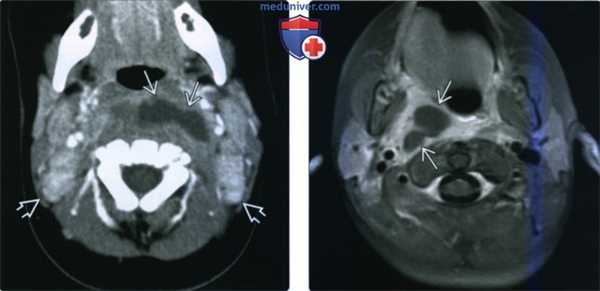

(Слева) МРТ Т2ВИ FS, аксиальная проекция. Исследование выполнено через 8 недель после завершения курса химиотерапии у пациента с плоскоклеточным раком небной миндалины. В ЗГП наблюдается жидкость. Гиперинтенсивные скопления жидкости также имеются в подкожной и глубокой клетчатке шеи. Черпалонадгортанные складки также отечные.

(Справа) КТ с КУ, аксиальная проекция. Скопление жидкостного содержимого в ЗГП. У пациента, недавно перенесшего переднюю дискэктомию, сформировалось псевдоменингоцеле (ликворея). Вдоль операционной раны жидкость распространяется кпереди в передние отделы шеи.

(Справа) КТ с КУ, аксиальная проекция. В заглоточном пространстве (ЗГП) имеется жидкостное содержимое В низкой плотности без периферического кольца накопления контраста. Причиной появления жидкости стал тромбоз правой внутренней яремной вены. Также отекли ткани правого сонного пространства и жировая клетчатка заднего шейного пространства. (Слева) КТ с КУ, аксиальная проекция. Жидкостное содержимое в заглоточном пространстве (ЗГП) без кольца накопления контраста. Можно определить причину отека: обратите внимание на целлюлит вокруг нижней челюсти и утолщение подкожной мышцы шеи, возникшие в результате инфекционного процесса со стороны зубов.

(Справа) МРТ Т2ВИ FS, аксиальная проекция. Заглоточное пространство (ЗГП) увеличено в размерах за счет тонкой симметричной полоски жидкости, интенсивность которой равна интенсивности ликвора. Причиной появления жидкости стал тромбоз правой внутренней яремной вены. Обратите внимание, что вместо участка выпадения сигнала в правой яремной вене определяется гиперинтенсивный сигнал.